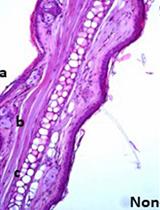

Cover of Malaria Journal, featuring study using the protocol.